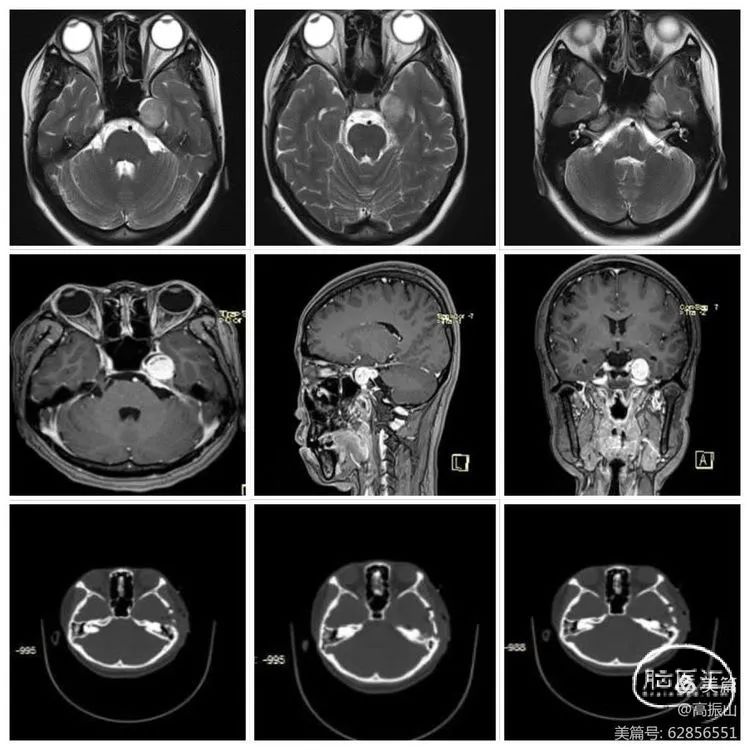

患者女性,23岁,因“左侧面部麻木1年余,加重1月”入院,查体:左侧颜面部感觉减退,咀嚼乏力,余(-)。

术前影像资料

对于术前影像资料的解读

首先我们明确一个观点就是鞍旁间隙和海绵窦的关系,鞍旁间隙的范围是从眶上裂的外侧端→圆孔的外侧端→卵圆孔的外侧端→三叉神经门的外侧端→三叉神经门的内侧端,向上延续为前后岩床韧带交点,再到后床突→鞍结节的外侧端→颈内动脉近环和远环→前床突→眶上裂的外侧端。从三叉神经门的内侧端向下到外展神经的硬膜端入口→后床突最后再回到眶上裂的外侧端,这些范围区间的硬膜结构叫鞍旁间隙,而在鞍旁间隙中的一些脏壁二层硬膜之间是分开,容纳了静脉窦,这些静脉窦叫做海绵窦。所以严格意义上来说Meckel腔是鞍旁间隙的结构。Meckel腔分为前壁和后壁,其中前壁是有两层脏层硬膜形成,而后壁是由一层脏层(海绵窦的外侧壁)和一层壁层硬膜(颅骨的骨膜)形成,所以Meckel腔实际是有四层硬膜构成。此例病例肿瘤位于Meckel的前后壁之间,其内侧有颈内动脉后垂直段,其后方是岩骨的三叉神经压迹,由颞骨CT可知三叉神经N压迹处骨质受压变薄,肿瘤已经有少许突破三叉神经门的迹象,由此可以大胆的推测肿瘤起源自三叉神经门附近,在肿瘤的颅底面可以看到肿瘤临近岩骨水平端ICA,并且肿瘤将颞叶钩回的尖部向后,向外,向上挤。(见下文示意图1、2、3)